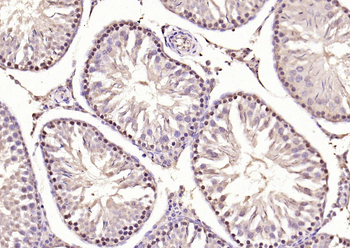

100 μl, 200 μl, 50 μlSMAD7 Rabbit Polyclonal Antibody [orb500819]

FC, ICC, IF, IHC-Fr, IHC-P, WB

Bovine, Porcine

Human, Mouse, Rat

Rabbit

Polyclonal

Unconjugated

100 μl, 200 μl, 50 μlPhospho-Smad3 (Ser213) Rabbit Polyclonal Antibody [orb106193]